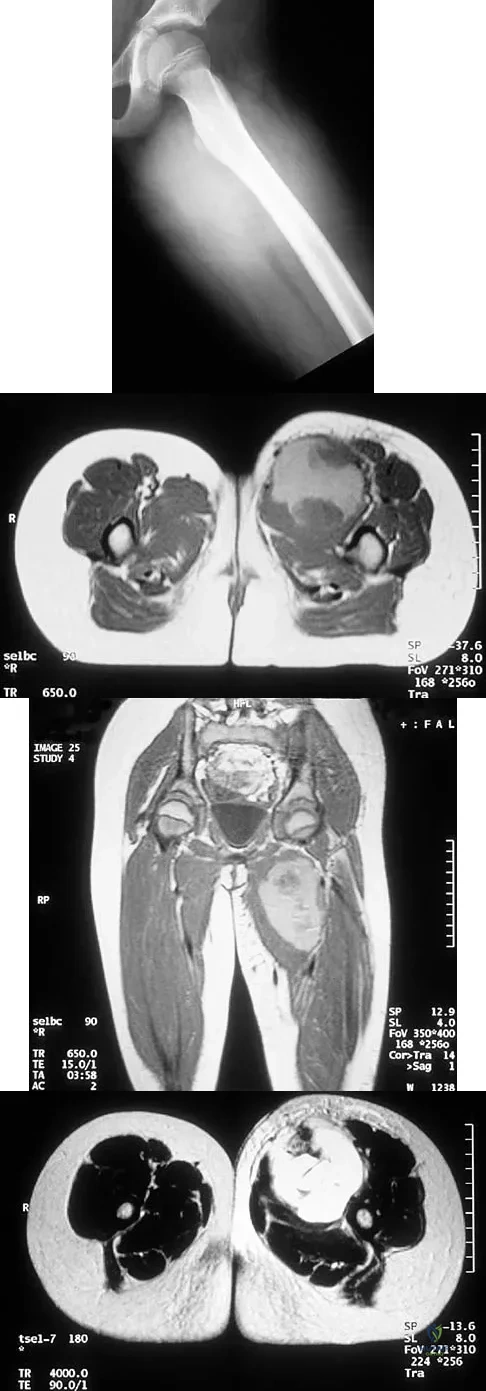

Figures 24a through 24c show the coronal T1-weighted, T2-weighted fat-saturated, and T1-weighted fat-saturated gadolinium MRI scans of the proximal thigh of a 52-year-old woman who reports a mass in the medial thigh and groin area. She notes that the fullness has grown in size over the course of many months. Based on these findings, what is the most likely diagnosis?

Explanation